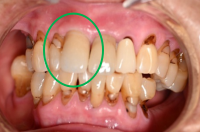

女性Aさん 50代(オールセラミック冠)

主訴

色が変わった上前歯をきれいにしたい。

治療内容

根管治療をし、オールセラミック冠を被せました。

所感

神経が取り除かれ、大きく詰め物がされていました。詰め物及び歯自体が変色し、虫歯になっていました。根管治療をし、ファイバーコアを入れ、オールセラミック冠を被せました。自分の歯は、捻転していましたが、被せ物により歯並びを改善することができました。

オールセラミック冠1本:¥104,500(税込)